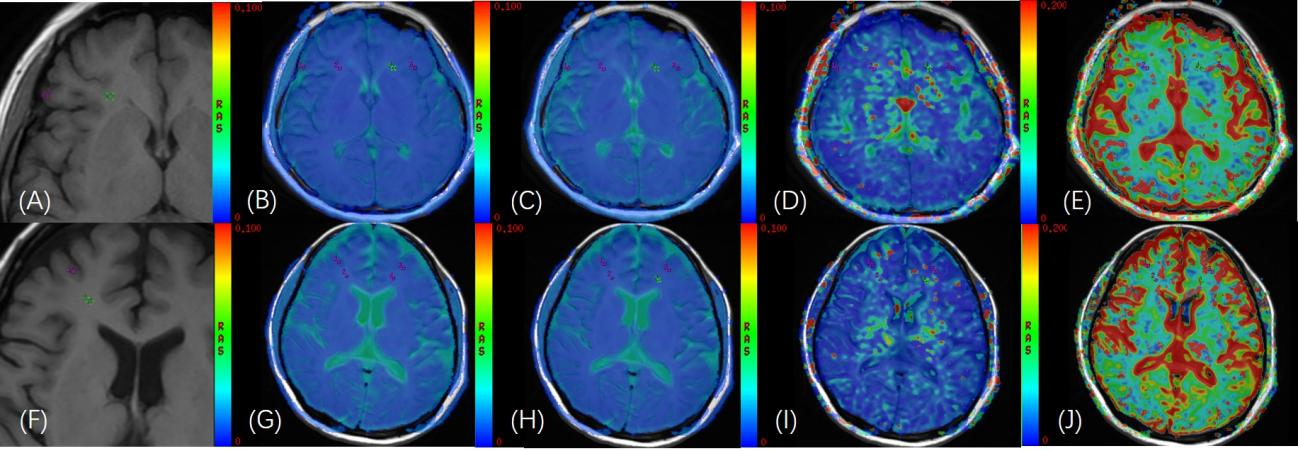

图1:正常志愿者(A)头颅轴位 T1WI 图像;(B)-(E)在轴位 IVIM功能像(sADC、D、D*、f图)与轴位 T1WI 融合图像上勾画双侧额叶的灰质、白质,(灰质:f =15.8%;白质:f =18.1%),ROI面积为8mm2。AL 患者(F)头颅轴位 T1WI 图像;(G)-(J)在轴位 IVIM 功能像(sADC、D、D*、f图)与轴位 T1WI 融合图像上勾画双侧额叶的灰质、白质,(灰质:f =1.37%;白质:f =6.5%),ROI面积为8mm2。

研究表明,AL患者灰质和白质的血流灌注参数f值均显著低于正常志愿者(z=-2.583,P =0.010;z=-2.923,P =0.003);脑组织灰质f值(7.08%)、白质f值(13.77%)是诊断AL的cutoff值。该研究结果首次发现AL患者脑血流灌注的异常。同时AL患者不同亚型大脑灰质和白质的D值不同,提示不同病理亚型AL脑组织微环境改变的异型性。